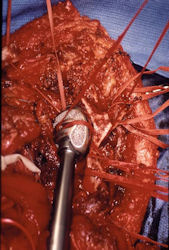

Limb-sparing surgery for osteosarcoma of distal femur – Intraoperative photos

In each case, the tumor and bone from which it arose were resected. This required meticulous dissection, mobilization and preservation of adjacent pertinent neurovascular structures. In each case presented here, the defect was reconstructed with a special modular segmental tumor prosthesis. This also replaces the adjacent joint in many instances.

Examples of radical limb sparing surgeries for osteosarcomas in various anatomic locations (distal femur, proximal tibia, proximal humerus, scapula)